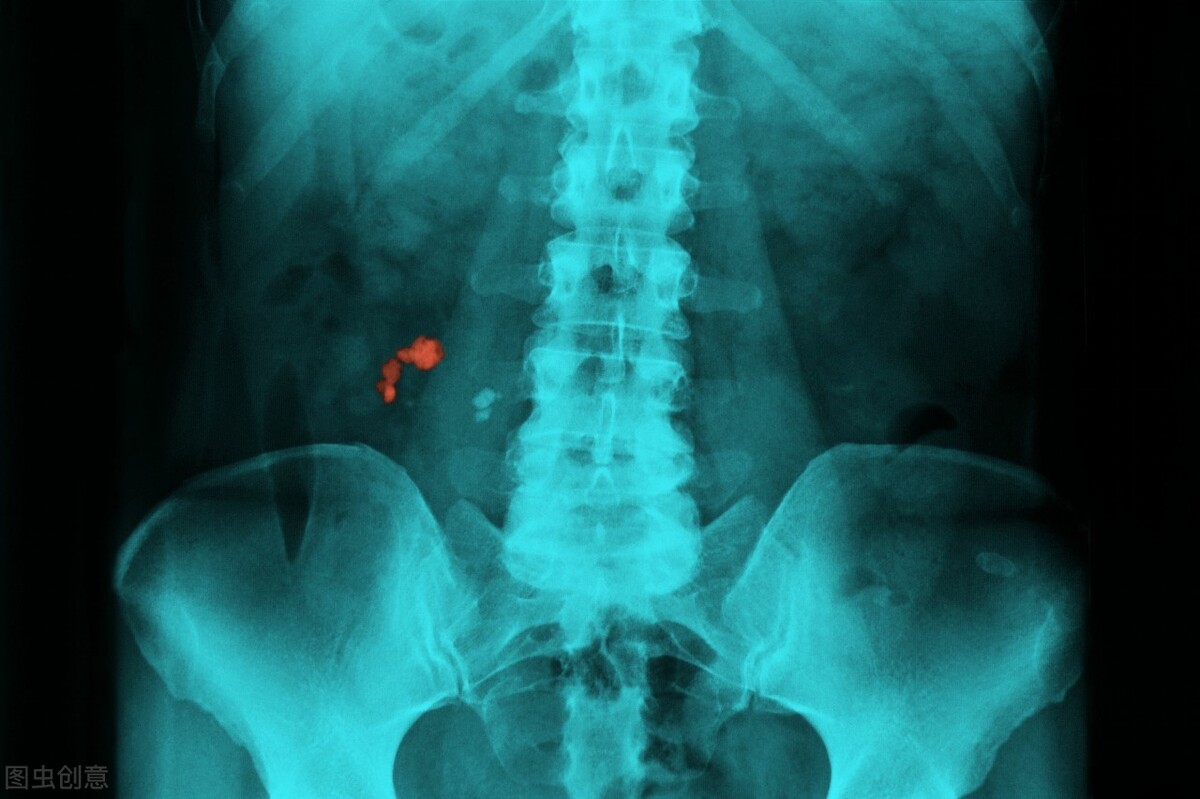

肾结石患者一开始可能不会出现任何症状,直到结石在肾脏移动或进入输尿管,这时可能会出现一种或多种症状。肾结石临床症状,主要包括: 腰痛(上腹部或背部及两侧不适)、血尿、尿频尿急尿痛、发热、恶心呕吐 等。肾结石诊断基于病史、查体、尿分析和影像学检查。临床上依疼痛的部位,严重程度(多为绞痛,反复节奏),结石致梗阻时引起后背痛疼。查体显示患者肋脊角压痛。尿常规可以看到红细胞明显增多,且红细胞形态为均一性。尿路平片是重要的一种检测手段,90%以上的结石为不透光结石,在尿路平片上表现为高密度影,但是结石小于2mm无法分辨。超声检查也是一种重要的手段,在超声上还能看到有无肾积水等梗阻表现,一些阴性结石(在X线上透光,如尿酸结石)在彩超上也能检查出来。泌尿系CT检查能够分辨出0.5mm的结石,并且能够显示任何成分的结石,包括阴性结石。